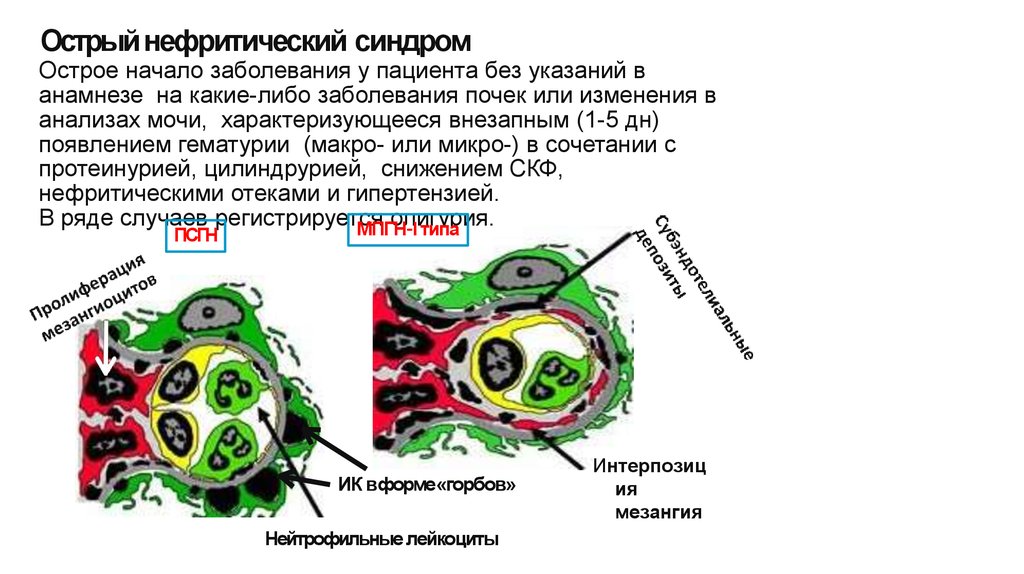

Механизм остро го диффузного гломерулонефрита